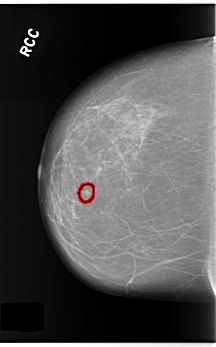

C_0253_1.RIGHT_CC

RIGHT_CC LINES 5896 PIXELS_PER_LINE 3656 BITS_PER_PIXEL 12 RESOLUTION 50 OVERLAY

FILE: C_0253_1.RIGHT_CC.OVERLAY

TOTAL_ABNORMALITIES 1

ABNORMALITY 1

LESION_TYPE CALCIFICATION TYPE PUNCTATE DISTRIBUTION CLUSTERED

LESION_TYPE MASS SHAPE OVAL MARGINS CIRCUMSCRIBED

ASSESSMENT 4

SUBTLETY 5

PATHOLOGY BENIGN

TOTAL_OUTLINES 1

BOUNDARY